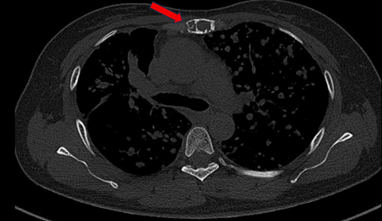

Bệnh nhân đi khám tại bệnh viện Bạch Mai được chụp cắt lớp vi tính lồng ngực phát hiện nhu mô thùy trên có khối đặc kích thước 40 x 35 mm, các nốt đặc đường kính <12 mm lan tỏa nhu mô hai phổi, ổ tiêu xương ức kích thước 31 x 13 mm.

Hình 1: Hình ảnh tổn thương phổi trước điều trị: nhu mô thùy trên có khối đặc kích thước 40 x 35 mm (mũi tên màu đỏ), các nốt đặc đường kính <12 mm lan tỏa nhu mô hai phổi (mũi tên màu xanh)